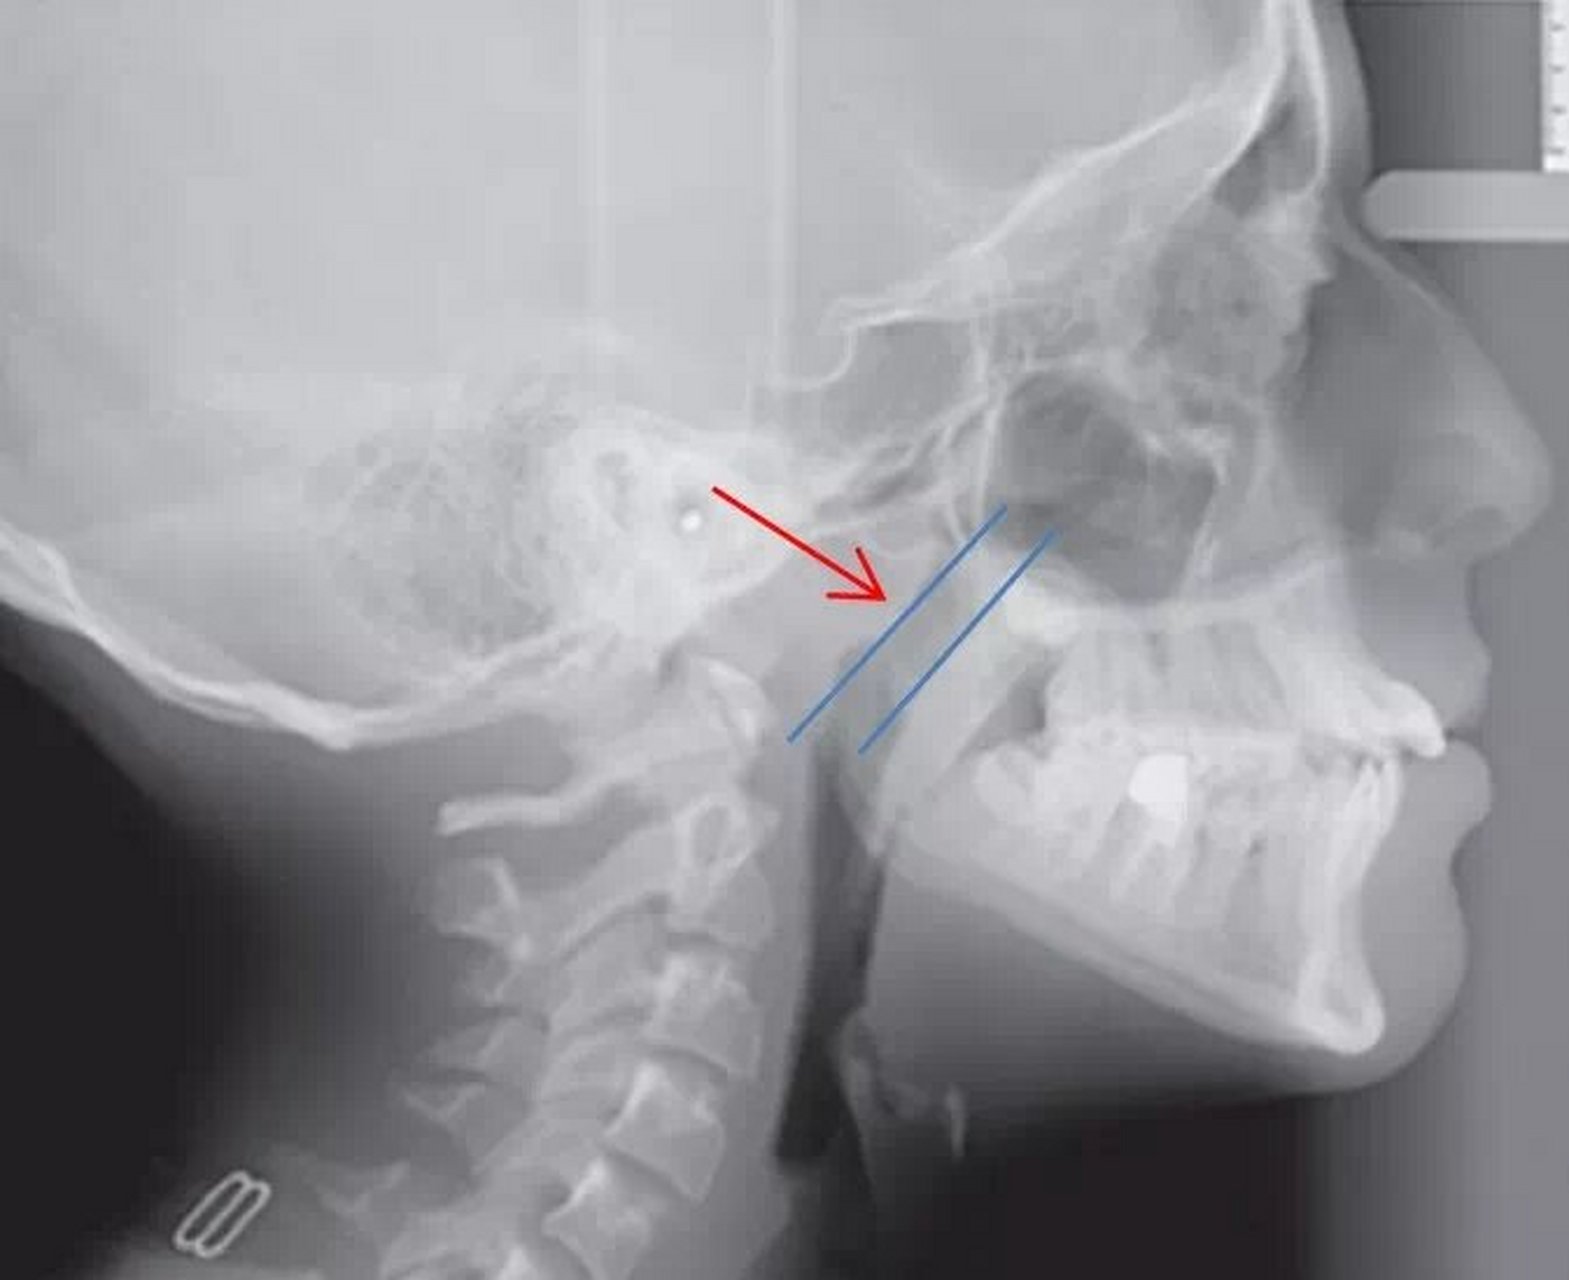

鼻咽侧位片示肥大的腺样体

腺样体肥大的测量:首选鼻咽侧位x线片.

腺样体-鼻咽腔比率a/n值:鼻咽侧位片的测量方法(一)患儿端坐或站立

鼻咽侧位片的测量方法(二)